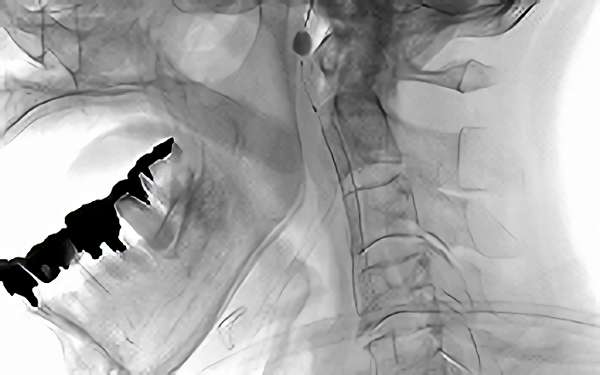

左内頚動脈狭窄症

手術前1

手術前2

手術中1

手術中2

手術後1

手術後2